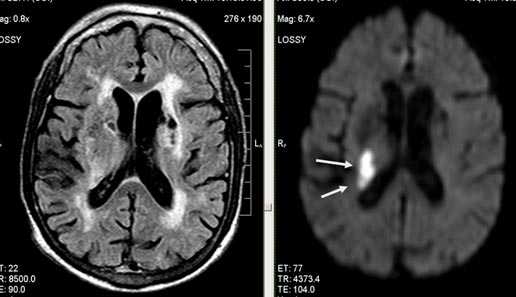

Бассейн кровоснабжения левой верхней мозжечковой артерии, острая стадия НМК.

Зона подострого ишемического НМК, в бассейне правой средней мозговой артерии. В режиме Т1 визуализируется симтом «вуалирования»- изоинтенсивность МР-сигнала.

Подострая стадия ишемического НМК. При внутривенном контрастировании определяется накопления КВ в бороздах на уровне зоны ишемии (гиральный тип усиления).

Зона хронического ишемического НМК, в бассейне левой задней мозговой артерии.

Ишемическое ОНМК, ствол мозга (подострый период)

Одно из преимуществ МРТ в оценке последствий инсульта - возможность визуализировать нисходящую Валлеровскую дегенерацию аксонов в стволе мозга и кортико-спинальном тракте на стороне поражения.

Кортикальное ишемическое НМК